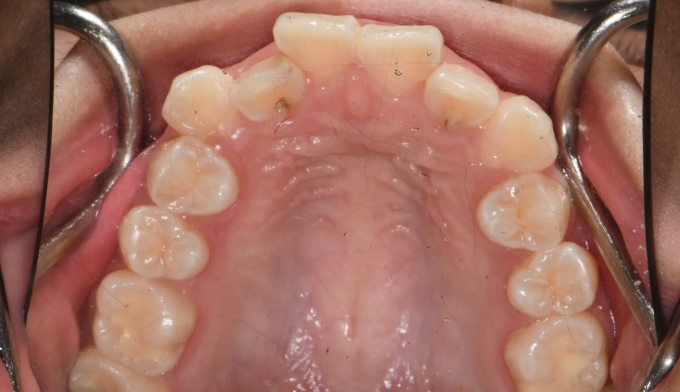

덧니

덧니가 있고, 입도 약간의 돌출감을 보입니다. 발치교정을 통해 이 모두를 해소할 수 있습니다.

치료도중, 환자 본인이 입이 너무 들어가서 얼굴 형태가 급격히 바뀌는것을 걱정하여 입을 최소한으로 집어넣기로 하였습니다. 따라서 발치 공간은 모두 치열을 가지런하는데 이용하기로 하였습니다.

발치후 교정하게 되면 교정을 위한 공간이 충분하므로 입의 전후방 위치를 마음껏 조정할 수 있다는 장점이 있습니다. 교정 중 입술의 모양이나 돌출정도를 바꾸고 싶다면 주치의에게 언제든 말씀해주세요!

교정기간은 20개월 소요되었습니다.